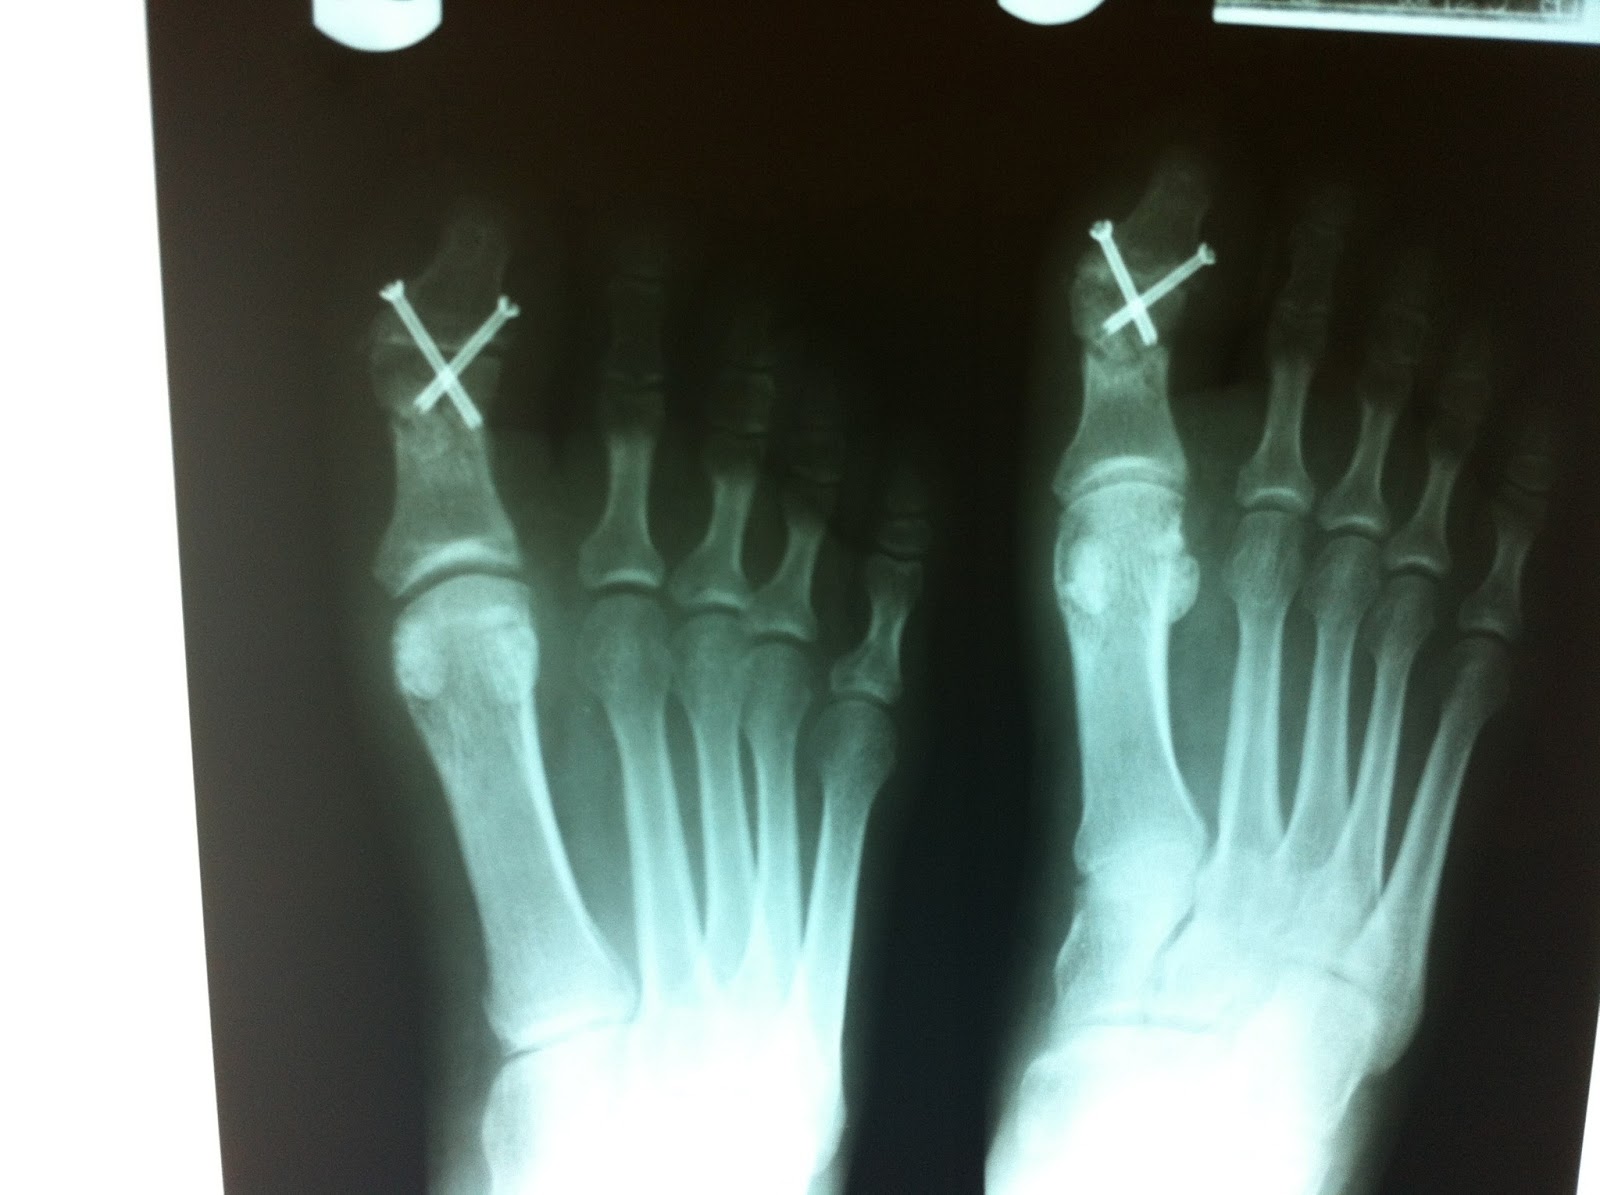

Running After Toe Fusion . It may help relieve pain and improve the. However in certain instances, when your bone is weaker than. In this post, i answer most people’s questions regarding the surgery. Hi had fusion op on left big toe sep 2014. Recovery is going to plan, however i am wondering when or if i can start jogging/running. Big toe joint fusion surgery is one of the most commonly performed foot and ankle procedures. Follow the instructions your surgeon gives you about putting weight on the foot. Most patients must use crutches after the. Who is a good candidate for big toe fusion? Big toe fusion surgery has gained traction over the years and is now a common procedure for podiatrists. How long does it take to recover? You may need big toe joint fusion surgery if you are suffering from big toe arthritis with symptoms of stiffness, swelling and inflammation. Most patients can walk after the fusion without putting weight down on the toe. Big toe fusion surgery is often recommended for patients suffering from big toearthritis and severe bunions. After a first mtp fusion, most people are able to return to an active lifestyle — including walking, hiking, biking, swimming, and jogging — without pain in their toe.

Running After Toe Fusion How long does it take to recover? Big toe fusion surgery is often recommended for patients suffering from big toearthritis and severe bunions. Recovery is going to plan, however i am wondering when or if i can start jogging/running. You may need big toe joint fusion surgery if you are suffering from big toe arthritis with symptoms of stiffness, swelling and inflammation. Who is a good candidate for big toe fusion? In this post, i answer most people’s questions regarding the surgery. After a first mtp fusion, most people are able to return to an active lifestyle — including walking, hiking, biking, swimming, and jogging — without pain in their toe. Carrying out these regular exercises after your big toe fusion surgery is essential to prevent stiffness in the rest of the foot, restore your range of. Most patients can walk after the fusion without putting weight down on the toe. Hi had fusion op on left big toe sep 2014. It may help relieve pain and improve the. However in certain instances, when your bone is weaker than. Most patients must use crutches after the. How long does it take to recover? Big toe joint fusion surgery is one of the most commonly performed foot and ankle procedures. Big toe fusion surgery has gained traction over the years and is now a common procedure for podiatrists.